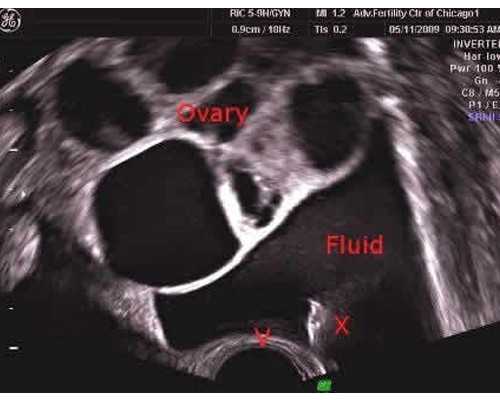

孕前优生可选查的项目有:子宫颈细胞学检查、TORCH筛查、阴道分泌物检查(包括常规检查、及淋球菌、沙眼衣原体检查)、甲状腺功能、血脂检查、75g口服葡萄糖耐量试验(高危妇女建议检测)、妇科彩超、心电图、胸片。